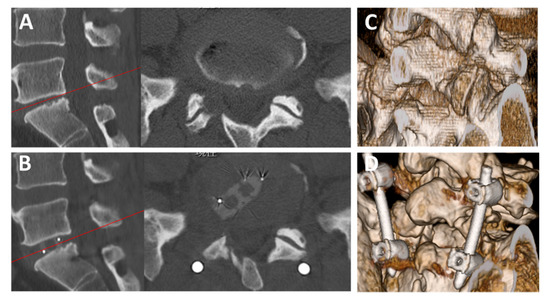

2.2. Surgical Technique

3. Results